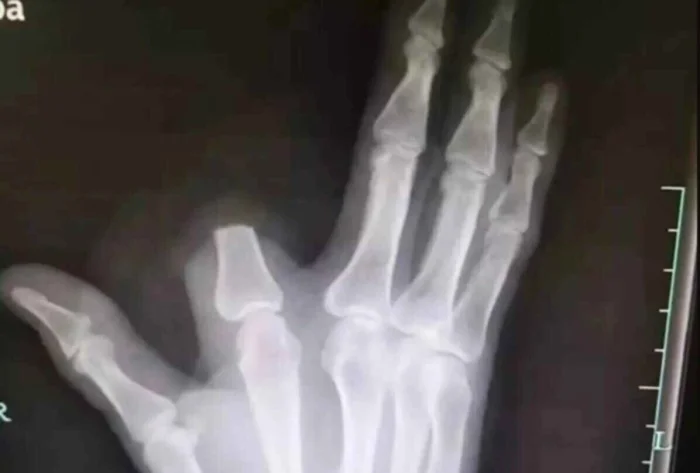

10. Американца укусила змея, и он решил отрубить себе палец. Врачи сказали, что это было неразумно